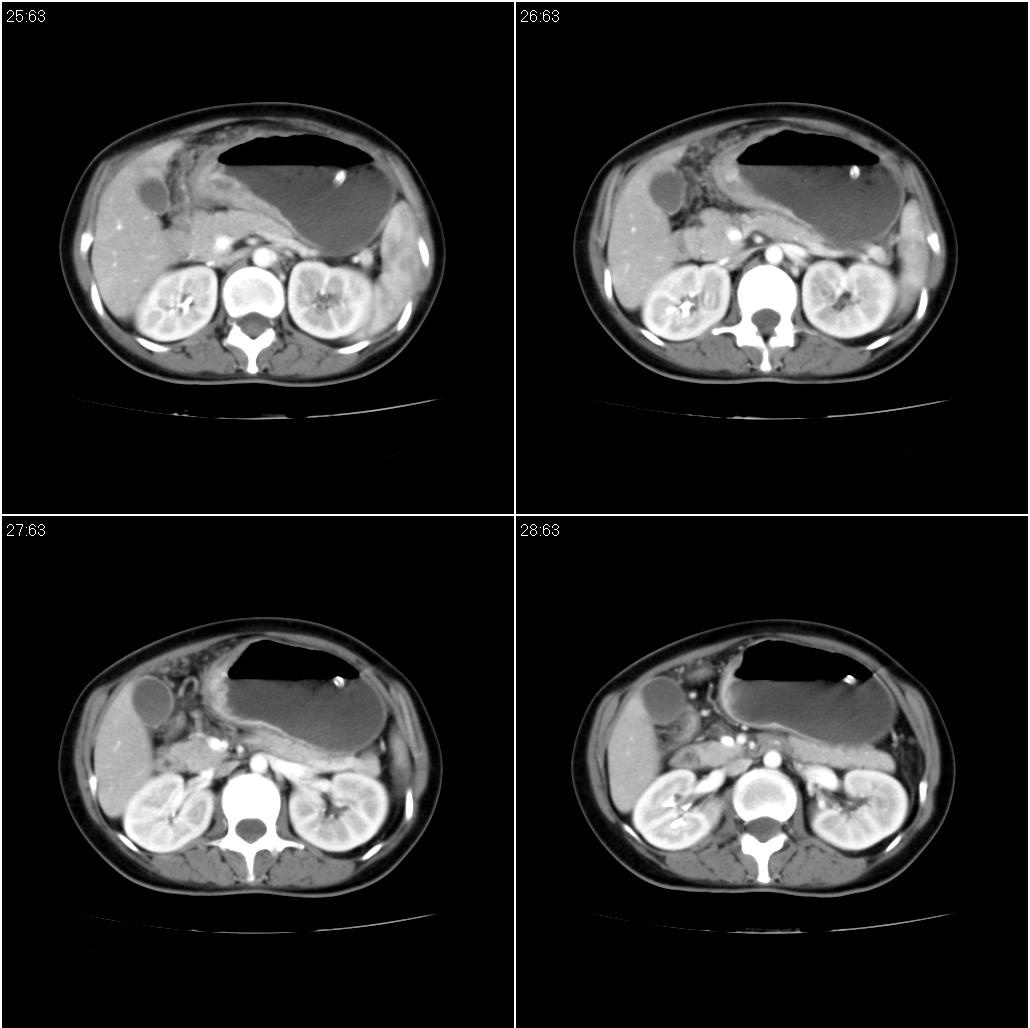

标题: CT21386:女性,33岁。4个月前因妊娠发现盆腔肿物。 [打印本页]

女性,33岁。4个月前因妊娠发现盆腔肿物。ca-125: 1100

胃幽门部癌伴小弯侧和腹腔淋巴结转移,胃内有胃管。

胃窦贲门胃小弯好像都厚啊 ,胃窦处比较明显,而且胃腔扩张明显,考虑胃癌伴梗阻。

考虑胃窦占位并肝门部淋巴结转移

考虑胃窦部胃癌伴小弯侧和腹腔淋巴结转移。

胃幽门部癌伴小弯侧和腹腔淋巴结转移,胃内有胃管